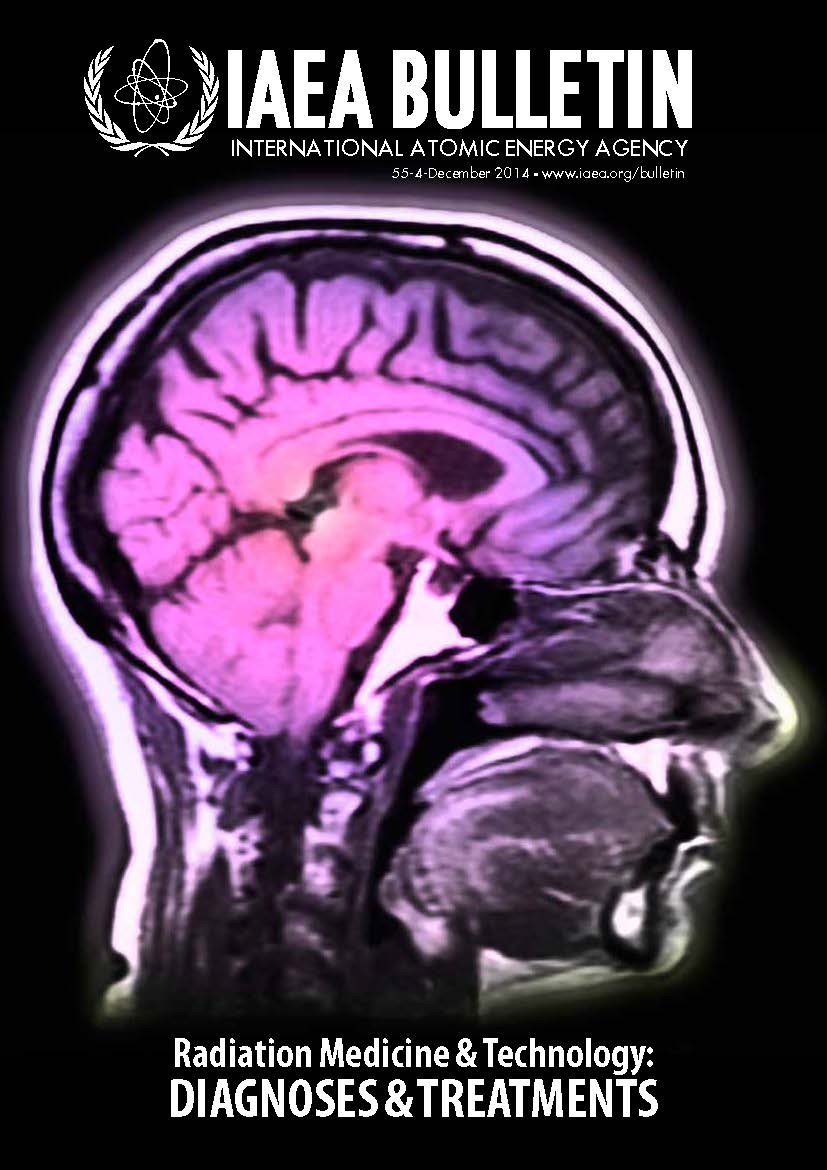

Radiation Medicine and Technology: Diagnoses and Treatments

Radiation medicine and technology contribute to the diagnosis and treatment of diseases and other health condition.